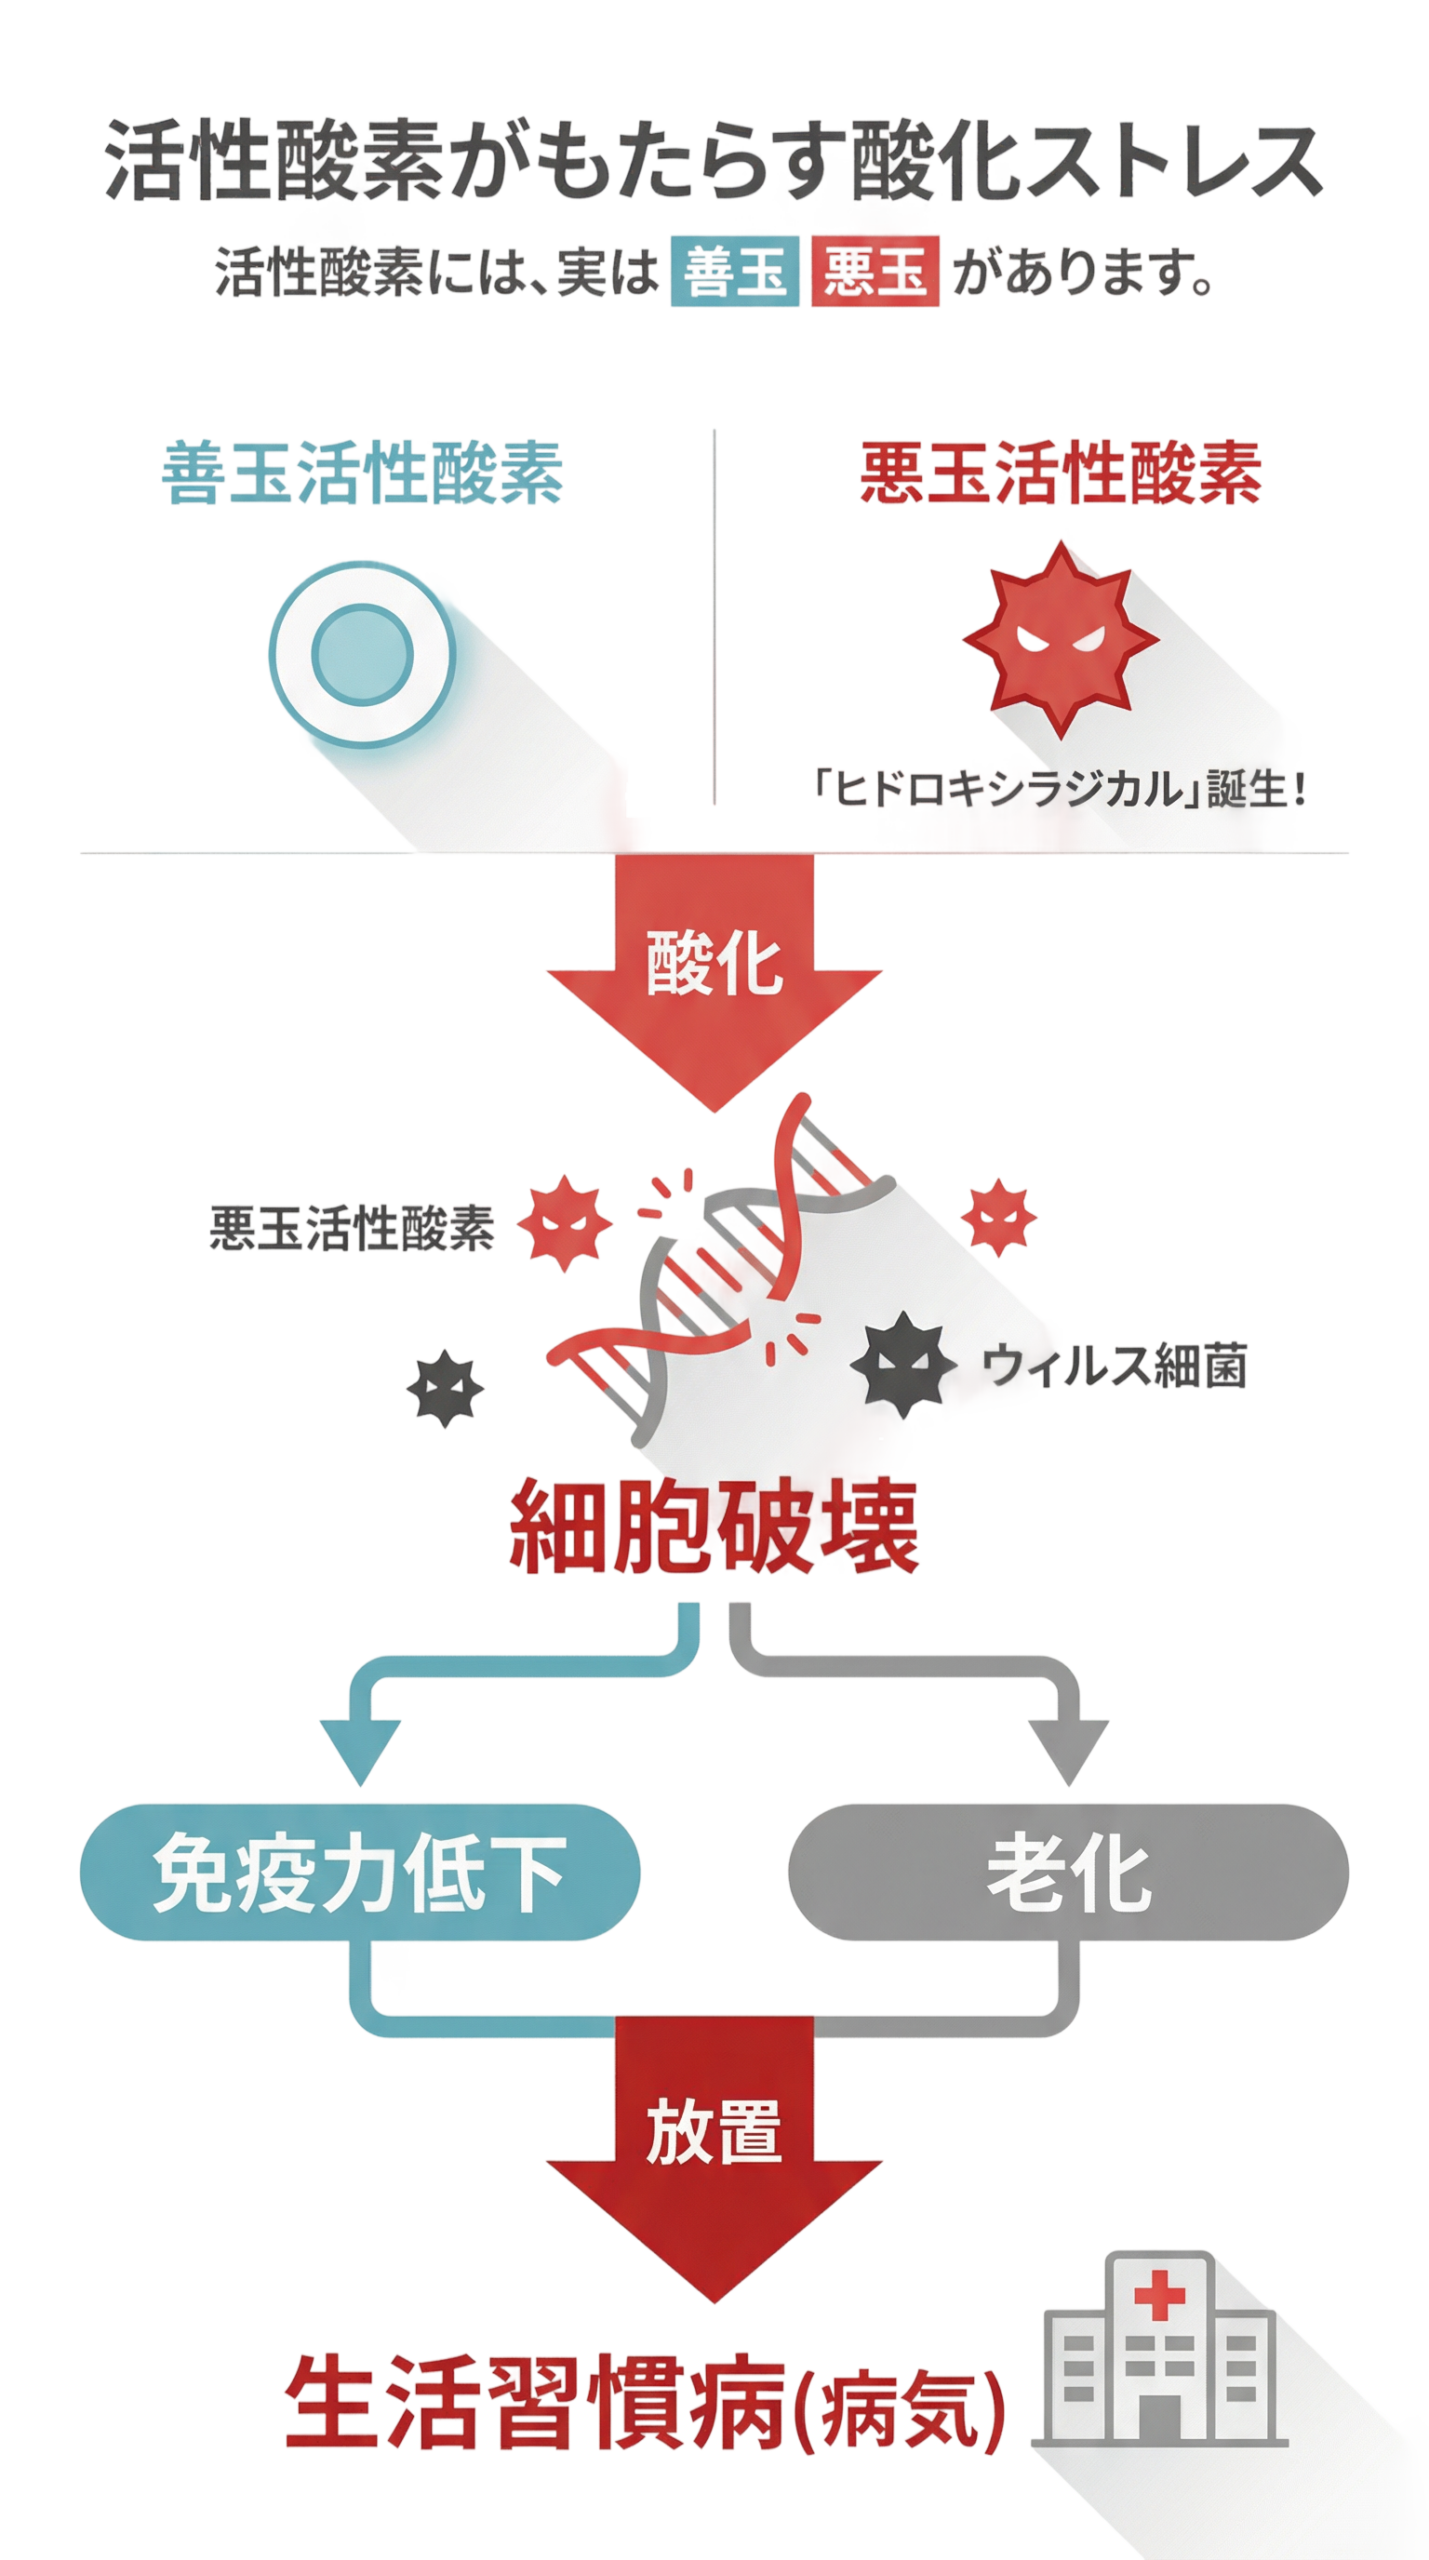

疲労やエイジングの原因は

「悪玉活性酸素」?

私たちの体内では、日々さまざまな

代謝活動が行われています。

その中で生まれる活性酸素が、

不調の一因になるとも言われています。

人は酸素を使ってエネルギーを作り出しますが、

その過程で活性酸素が発生することがあります。

善玉活性酸素は、体内に侵入した細菌やウイルスを攻撃したり、

細胞同士の情報伝達をサポートするなど、体にとって重要な働きを担っています。

しかし、過度なストレスや生活習慣の乱れ、紫外線、喫煙、過度な飲酒などの影響により、

体内で活性酸素が過剰に発生することがあります。

その中でも特に増加するとされるのが「悪玉活性酸素」です。

悪玉活性酸素は、健康な細胞まで攻撃して酸化を引き起こし、

さまざまな不調や老化の要因になると考えられています。

この状態は一般的に「酸化ストレス」と呼ばれています。

特に反応性が高く酸化力の強い「ヒドロキシラジカル」は、

細胞のDNAや脂質を酸化させ、遺伝子にダメージを与える可能性があります。

これが、がんをはじめとする生活習慣病や動脈硬化、

糖尿病などの発症リスクに関係しているといわれています。